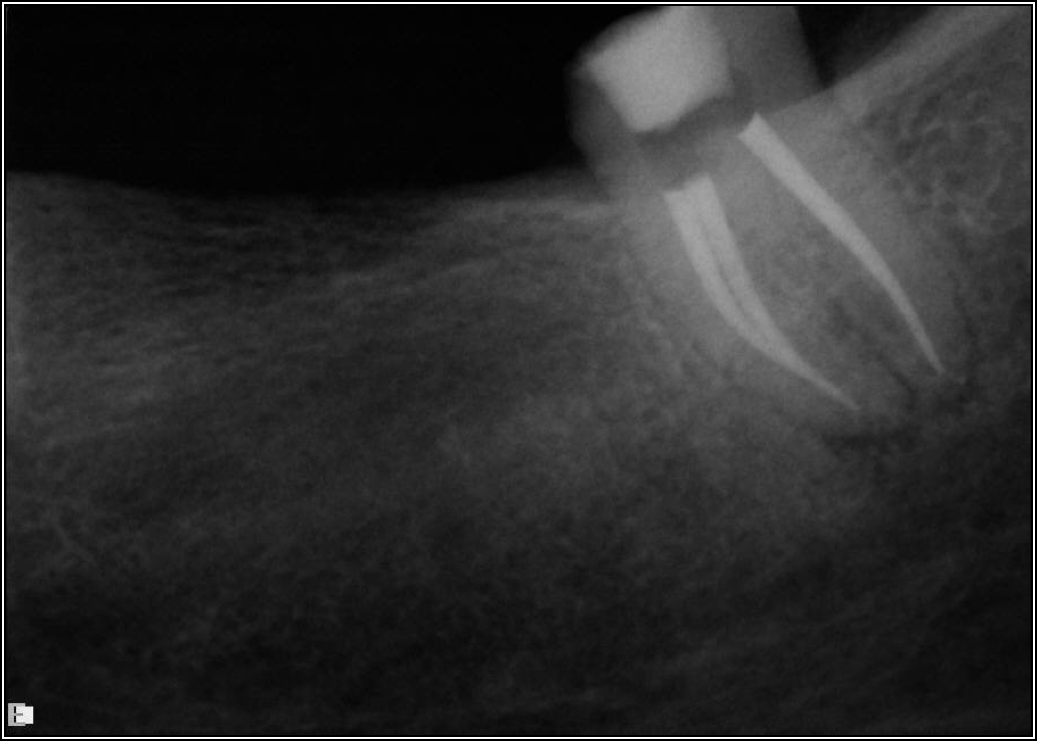

If a tooth stands alone, greater forces will be placed on it because it has no adjacent teeth to provide support. This situation will affect the decision-making process for placing a post. Figure 3 shows a tooth that was on an island and would be having three implants placed in front of it. The tooth would take a much greater beating than another tooth that had support proximally. Even though it had a good root canal, the clinician would need to account for whether the tooth would last until the implants integrated. Figure 4 shows a case that would quickly proceed to implants. The patient had a less-than-ideal bridge for over a decade, with decent endodontics and functionality. There was also an overhang on the premolar. The post was not ideal in this case because there was one distal canal and not all the gutta-percha was removed from it. An intimate fit should be the goal with the post and the walls. Whether using a threaded or non-threaded post, there should not be excess gutta-percha because it is not as solid as the tooth and will lead to greater movement. That movement on the tooth and bridge will create too much force and result in demise.

Fig 4. Case that quickly would proceed to implants.

Figure 4